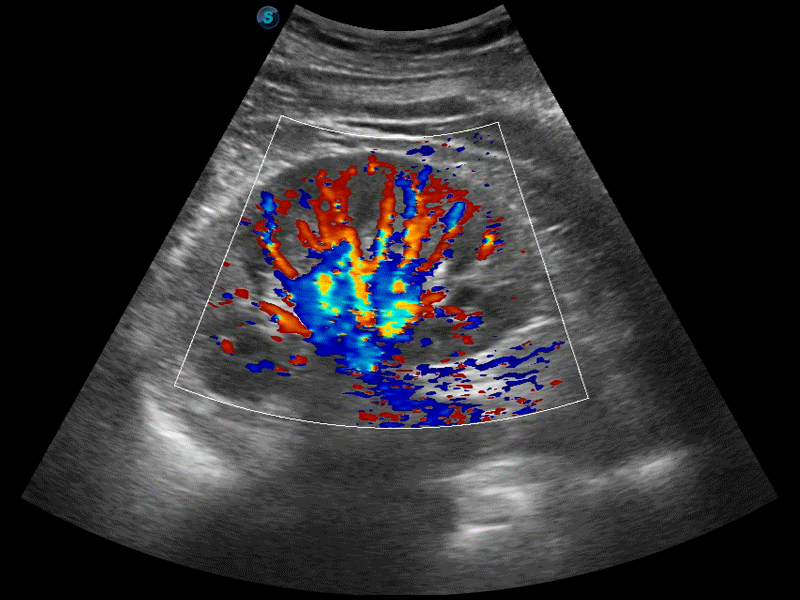

高分辨率血流成像技術(shù)提高了對(duì)低速血流信號(hào)的檢測(cè)能力。在提高空間分辨率的同時(shí),也克服了血流外溢現(xiàn)象,為用戶(hù)提供更加真實(shí)的血流動(dòng)力學(xué)信息。